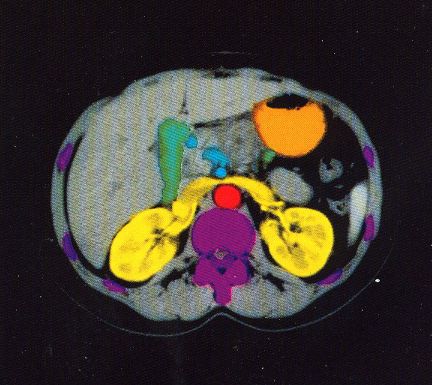

These photos of the Voxelscope II screen are typical of the types of rendering provided by the system.

Voxelscope II Screen Shots. Combination of 3-D Shaded Surface, Multiplanar Reformatting, and Segmentation